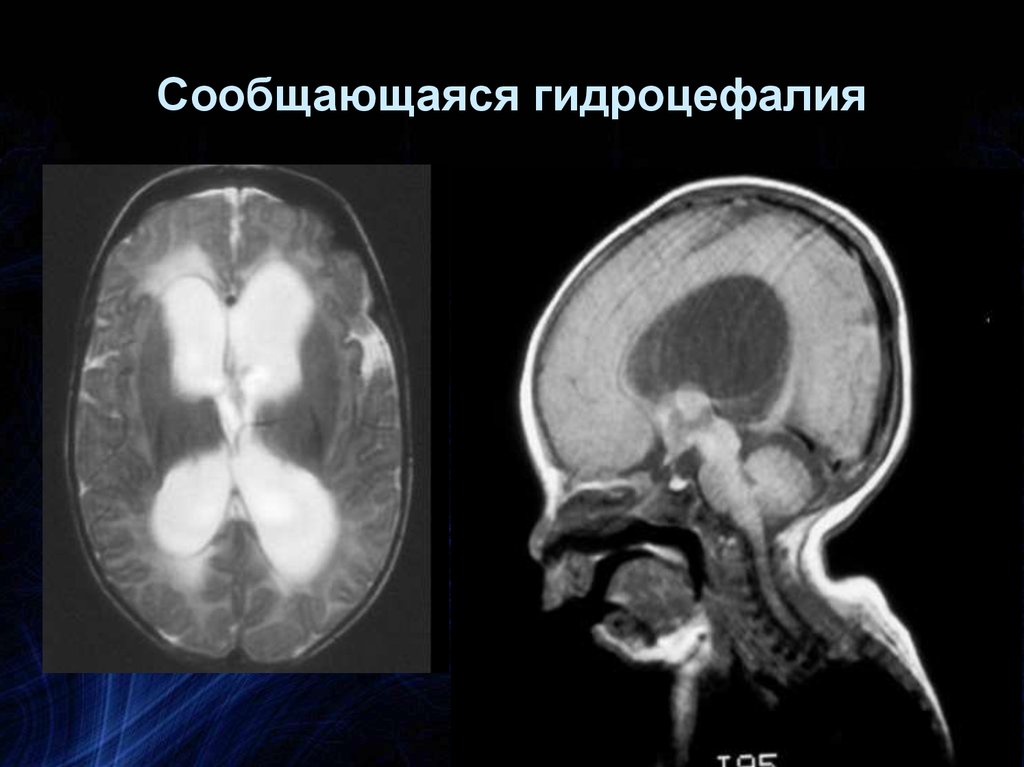

Признаки умеренно выраженной наружная

Признаки умеренно выраженной наружная 113 фото